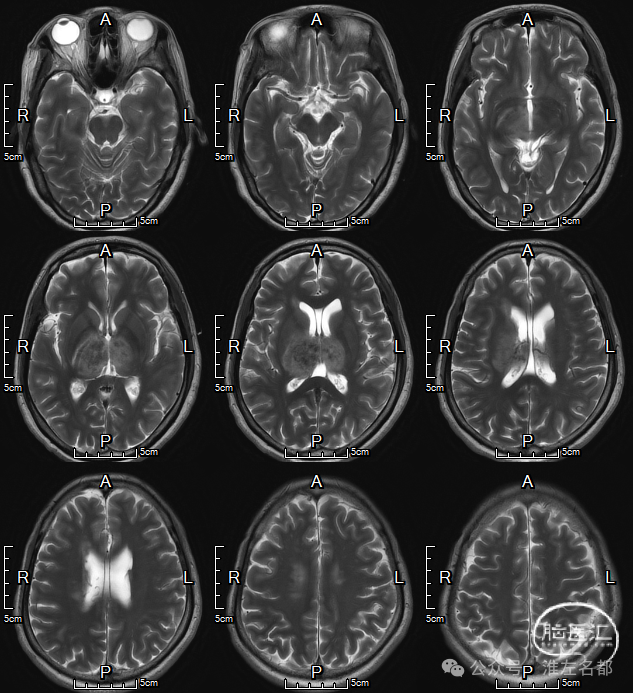

颅脑MRI

2024-9-25

T2

双侧丘脑和右侧内囊-间脑淤血性梗死、水肿和伴渗血。

增强MRV:左侧横窦-乙状窦显影纤细;上矢状窦和右侧横窦-乙状窦充盈缺损;脑深部静脉和直窦未见显影。

SWI:双侧丘脑渗血改变,右侧基底静脉和大脑中静脉血栓。